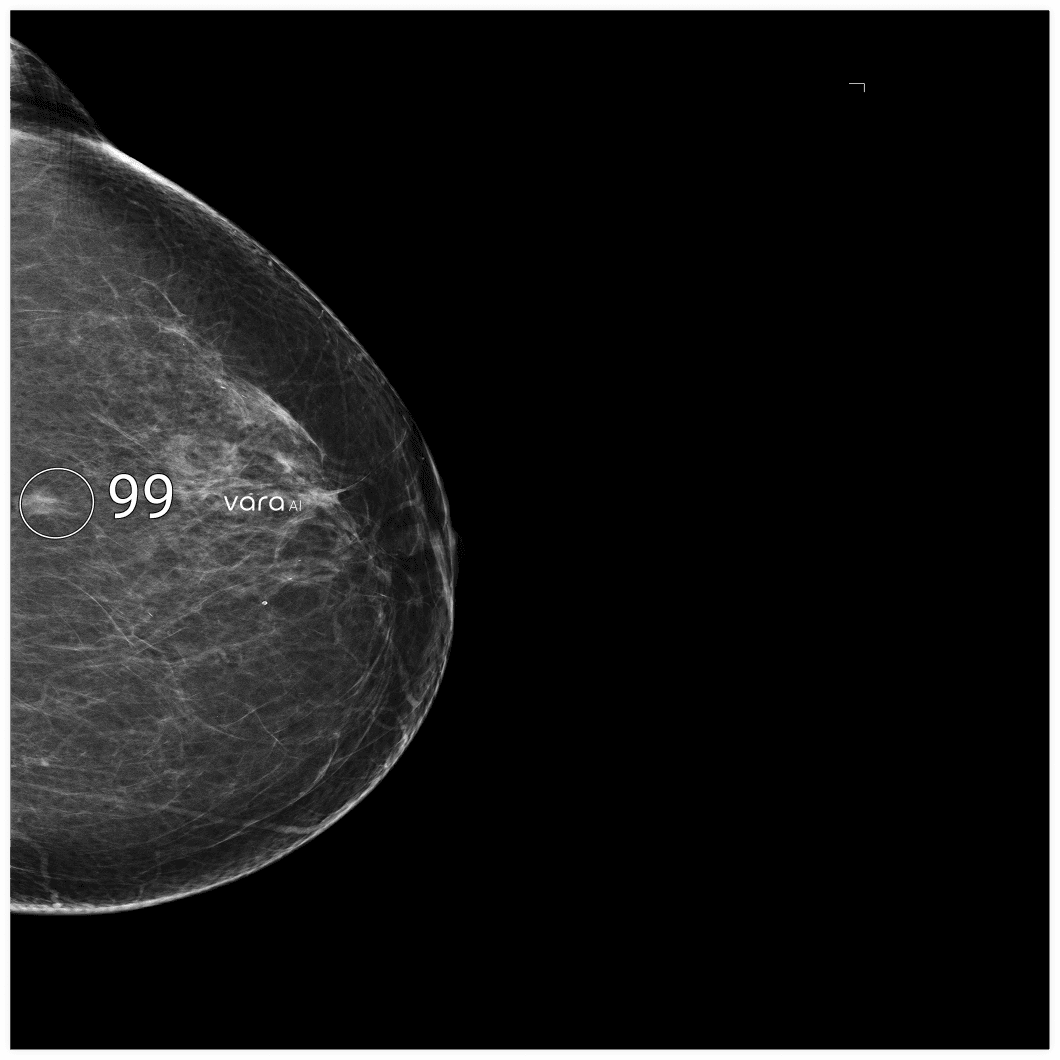

CAD Marking

On the S2D view — giving radiologists a "map" of where to focus when they scroll through the 3D stack.